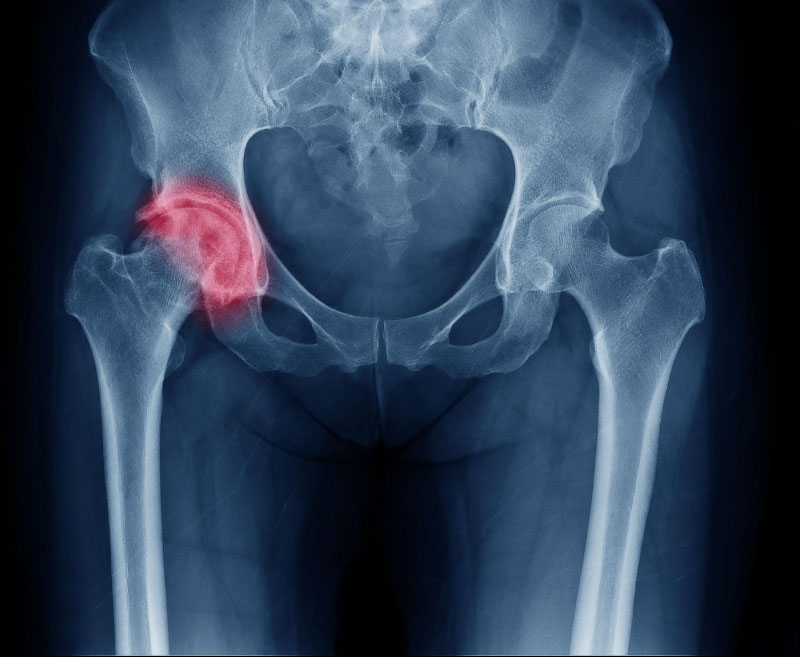

Chấn thương là những tổn thương thể chất do ngoại lực sinh ra, bao gồm tai nạn, ngã, bị đánh,… Tình trạng đau khớp háng bên phải có thể bắt nguồn từ một số chấn thương bao gồm: gãy xương, rách sụn viền khớp háng, trật khớp,… khiến khớp háng bên phải đau nhức, sưng, hạn chế vận động. Tùy thuộc vào từng tình trạng cụ thể mà bác sĩ sẽ chỉ định phương pháp điều trị phù hợp.

Biến dạng khớp háng xảy ra khi cấu trúc của khớp bị thay đổi do tình trạng tổn thương kéo dài và không được điều trị kịp thời. Điều này có thể ảnh hưởng nghiêm trọng đến chức năng của khớp, gây trở ngại khi thực hiện những chuyển động cơ bản và làm giảm chất lượng cuộc sống. Ngoài ra, biến dạng khớp cũng khiến khớp mất khả năng nâng đỡ cơ thể.

Chẩn đoán đau khớp háng phải nhằm mục đích xác định tình trạng, mức độ và nguyên nhân gây bệnh. Bác sĩ sẽ chỉ định người bệnh thực hiện một số phương pháp chẩn đoán bao gồm: